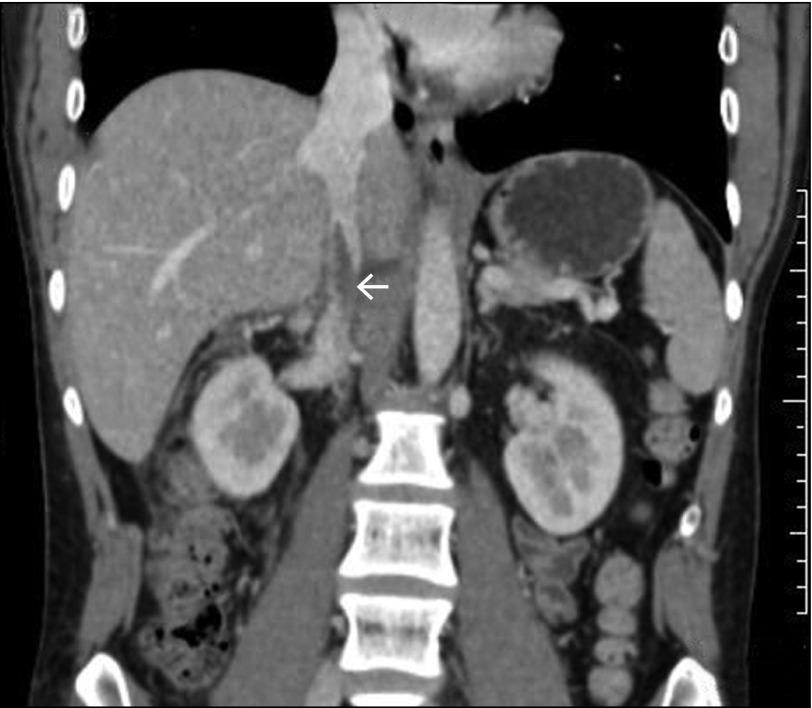

Acute pancreatitis is an inflammatory disorder often associated with various complications. Approximately one fourth of patients with acute pancreatitis develop vascular complications, of which venous thrombosis forms a major group. Extrasplanchnic venous thrombosis is less common, and simultaneous renal vein and inferior vena cava thrombosis is reported only twice. We report a case of alcohol-related acute pancreatitis complicated by simultaneous renal vein and inferior vena cava thrombosis.

急性胰腺炎是一种常伴有各种并发症的炎症性疾病。大约四分之一的急性胰腺炎患者会出现血管并发症,其中静脉血栓形成是主要类型。肝外静脉血栓形成较少见,同时累及肾静脉和下腔静脉的血栓形成仅报道过两例。我们报告一例酒精相关性急性胰腺炎并发肾静脉和下腔静脉同时血栓形成的病例。